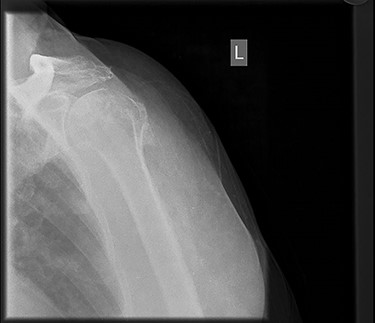

Six months post-surgery—profound loss of joint space and superior subluxation.

X-ray images 6 months later showed the devastating effect of the infection with a profound loss of joint space and superior subluxation in keeping with loss of rotator cuff muscles.